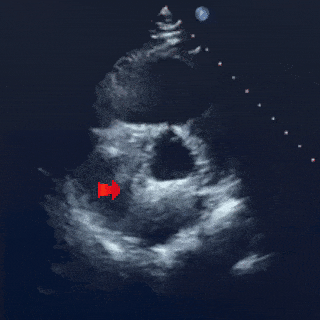

四腔心切面下

封堵器左右盘面骑跨房间隔两侧形态位置良好

释放后影像

最后封堵器盘面稳固扣合,形态扁平且位置良好,封堵成功